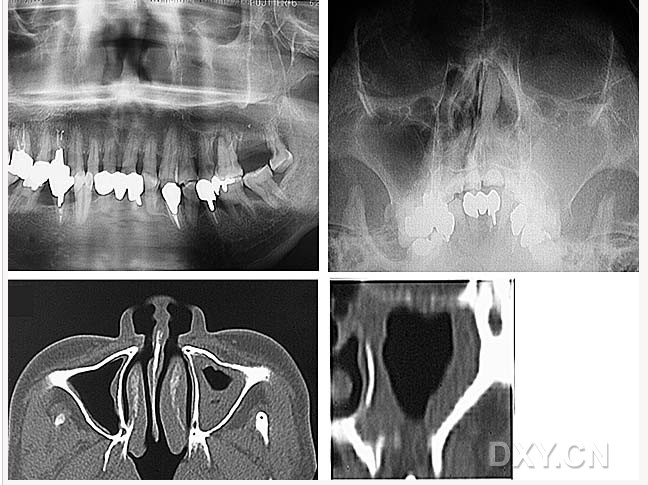

大理石骨?。ㄏ骂M骨有明顯的骨化影像,恒牙埋伏)

鼻竇炎(注意不要誤診呀)

良性成牙骨質(zhì)細胞瘤